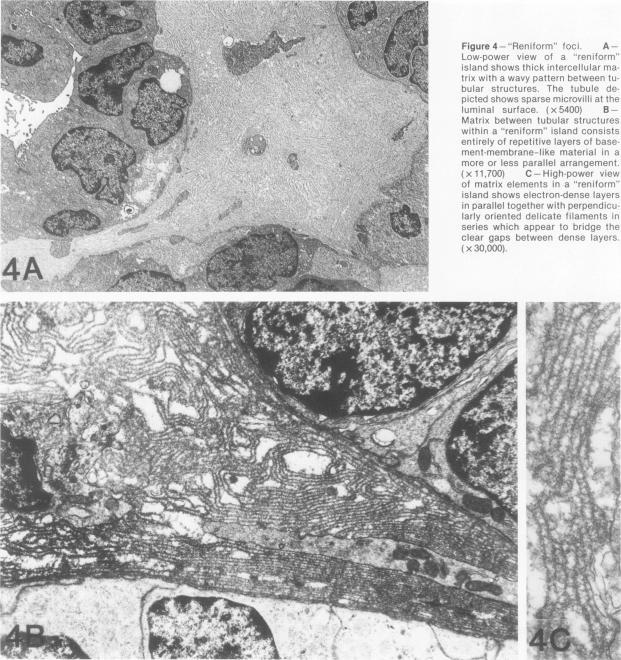

Eight examples of nephroblastoma induced transplacentally in the partially inbred IIIVO/J strain of rabbit by a single intraperitoneal (60 mg/kg) dose of N-ethylnitrosourea (ENU) were studied by transmission electron-microscopy. At the light-microscopic level the ENU-induced tumors displayed the complex array of histotypic components described in a previous report (Hard GC, Fox RR: Histologic characterization of renal tumors (nephroblastomas) induced transplacentally in IIIVO/J and WH/J rabbits by N-ethylnitrosourea. Am J Pathol 1983, 113:8-18) namely, blastema, tubular profiles, "reniform" islands, glomeruloid bodies, squamoid foci, fascicles of mesenchymelike tumor cells, and an increasing fibrocollagenous stroma. Ultrastructurally, blastemalike cells were undifferentiated forms resembling metanephric blastema. Tubular profiles of varying development were typified by very prominent apical junctional complexes and a basal lamina, but no organized brush-border. "Reniform" islands were groups of more maturely formed tubules associated with the production of an interstitial matrix consisting almost solely of multilamellar basement membrane. Glomeruloid bodies were invaginations of small podocytelike cells, with a profusion of thin cytoplasmic processes resembling foot processes, and internal, homogeneous areas of basement membrane continuous with that surrounding the entire structure. As such, these structures were consistent with primitive attempts at glomerular differentiation but without vascular or mesangial elements. The squamoid foci were representative of true squamous differentiation in comprising cells filled with intermediate filaments and interconnected by lateral interdigitations and multiple, well-formed desmosomes. Spindle-shaped tumor cells disposed in fascicles, which could have been interpreted as bipotential differentiation into secondary mesenchyme at the histologic level, differed from the blastemal cell type only in shape. Ultrastructurally, the fascicles, in most cases, consisted of thin, basement-membrane-invested ribbons of attenuated cells enclosing small lumens sealed by intercellular junctions, suggestive of abortive tubule formation. Tumor cells disposed in fascicles therefore conformed to the same epithelial lineage as the other neoplastic components of these tumors. In contrast, cellular elements of the fibrocollagenous stroma--namely, fibroblasts, vascular endothelial cells, and scattered mononuclear inflammatory cells--could be clearly discriminated from the various tumor cell components on morphologic grounds, constituting a host reaction.(ABSTRACT TRUNCATED AT 400 WORDS)

通过腹腔注射单次剂量(60毫克/千克)的N-乙基亚硝脲(ENU),在部分近交系IIIVO/J兔中经胎盘诱导产生了8例肾母细胞瘤,采用透射电子显微镜对其进行了研究。在光学显微镜水平上,ENU诱导的肿瘤呈现出先前报告中所描述的复杂组织学成分组合(Hard GC,Fox RR:N-乙基亚硝脲经胎盘诱导IIIVO/J和WH/J兔产生的肾肿瘤(肾母细胞瘤)的组织学特征。《美国病理学杂志》1983年,113:8 - 18),即胚基、管状结构、“肾形”岛、肾小球样体、鳞状病灶、间充质样肿瘤细胞束以及逐渐增多的纤维胶原基质。超微结构上,胚基样细胞是未分化的形式,类似于后肾胚基。不同发育阶段的管状结构以非常突出的顶端连接复合体和基底膜为特征,但没有有组织的刷状缘。“肾形”岛是一组形成更成熟一些的小管,伴有几乎仅由多层基底膜组成的间质基质的产生。肾小球样体是小足细胞样细胞的内陷,有大量类似于足突的细细胞质突起,以及内部均匀的基底膜区域,与围绕整个结构的基底膜连续。因此,这些结构与肾小球分化的原始尝试一致,但没有血管或系膜成分。鳞状病灶代表真正的鳞状分化,其细胞充满中间丝,通过侧向交错和多个形成良好的桥粒相互连接。排列成束的梭形肿瘤细胞,在组织学水平上可被解释为双潜能分化为次级间充质,与胚基细胞类型仅在形状上有所不同。超微结构上,在大多数情况下,这些束由包裹着小腔隙的、基底膜包绕的、变薄细胞的细带组成,小腔隙由细胞间连接封闭,提示小管形成失败。因此,排列成束的肿瘤细胞与这些肿瘤的其他肿瘤成分属于相同的上皮谱系。相比之下,纤维胶原基质的细胞成分,即成纤维细胞、血管内皮细胞和散在的单核炎性细胞,在形态学上可与各种肿瘤细胞成分清楚地区分开来,构成宿主反应。(摘要截选至400字)